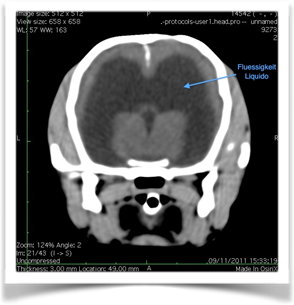

- Risonanza magnetica: è l’esame di diagnostica per immagini più affidabile per il riconoscimento di patologie prosencefaliche che causano crisi convulsive.

- Tomografia computerizzata (TC): può mettere in evidenza molte lesioni prosencefaliche ed è l’esame di prima scelta nei pazienti traumatizzati. E’ scarsamente sensibile nell’evidenziare le lesioni infiammatorie o metaboliche non consentendo una differenziazione ai fini della scelta terapeutica da mettere in atto.